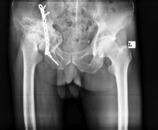

Combined fractures of the femoral head and acetabulum due to hip gunshot injuries (GSI) are rare, and there is no preferred treatment option. We present a 35-year-old male patient who sustained a right hip GSI. Delayed THA with a two-step sequential approach is a feasible management in this situation to manage soft tissue and decrease infection rate. At a 1-year follow-up visit, the pain was relieved, and the function improved significantly, and he had no complaints.

因髋部枪伤(GSI)导致的股骨头和髋臼联合骨折较为罕见,且尚无首选治疗方案。我们报告一名35岁男性患者,其遭受了右髋部枪伤。在这种情况下,采用两步序贯方法进行延迟全髋关节置换术(THA)是一种可行的治疗方式,可处理软组织并降低感染率。在1年的随访中,疼痛缓解,功能显著改善,患者无任何不适主诉。